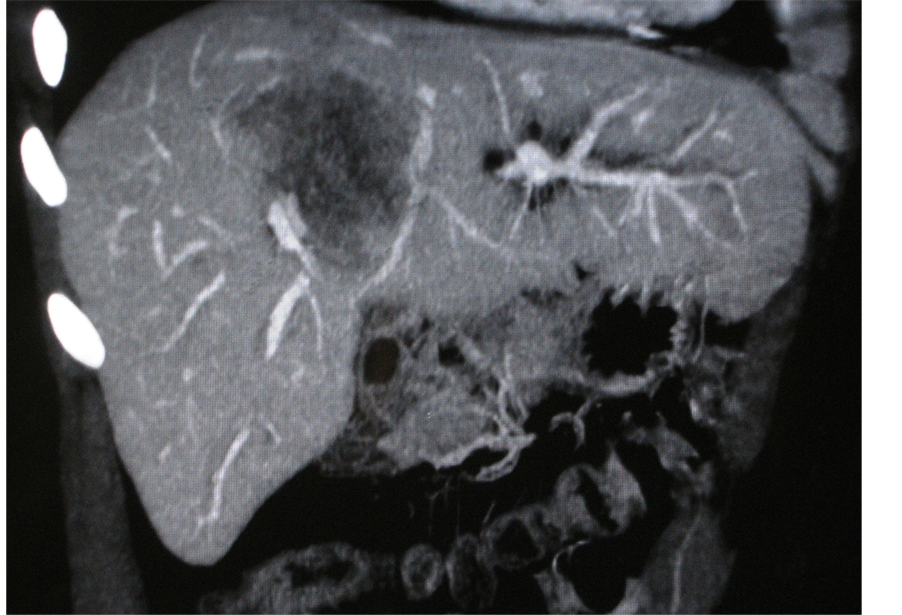

Few years ago, a 30-year-old man with a long history of moderate Crohn’s disease was operated on at our surgical department for a large intrahepatic cholangiocarcinoma (Figure 1) and died from the disease one year later. He was treated with Azathioprine along with Infliximab for a short period of time. An induction regimen of 3 single-dose infusions of 5 mg per kg of Infliximab at 0, 2, and 6 weeks was used. Patient slightly improved but 3 months later developed painless obstructive jaundice and was diagnosed with cholangiocarcinoma.

Figure 1. CT scan showing in segment 8 and 4 a large liver mass measuring 60 × 85 mm in the axial axes and about 9 cm in height, associated with multiple smaller peripheral lesions and responsible for an important dilatation of bile ducts.